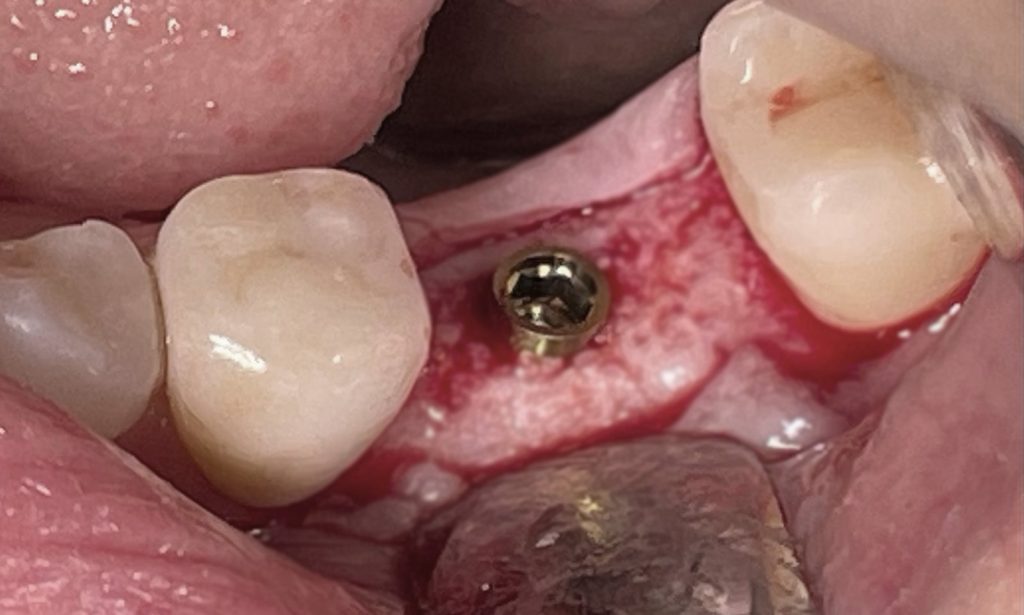

In questo caso specifico, con l’impianto PRAMA di Sweden&Martina è possibile gestire il posizionamento in senso apico-coronale per poter tenere la connessione impianto/abutment sovracrestale; in questo modo è possibile tenere l’eventuale infiltrato batterico lontano dal tessuto osseo.

Ne deriva un miglior risultato nel tempo e si riduce il rischio di perimplantiti.